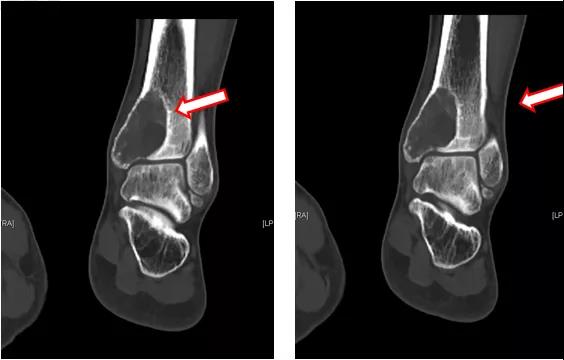

地舒单抗治疗后,复查左踝MRI提示:左侧胫骨内侧髁关节面下占位性病变,与2020-09-03 MRI对比,胫骨远端病变内T2WI高信号范围减小(图4~6)。

图4:左踝MRI(地舒单抗治疗后)

图5:左踝MRI(地舒单抗治疗后)

图6:左踝MRI(地舒单抗治疗后)

进一步完善CT检查提示:胫骨远端病变内不规则高密度影,成骨明显(图7~9)。

图7:左踝CT(地舒单抗治疗后)

图8:左踝CT(地舒单抗治疗后)

图9:左踝CT(地舒单抗治疗后)